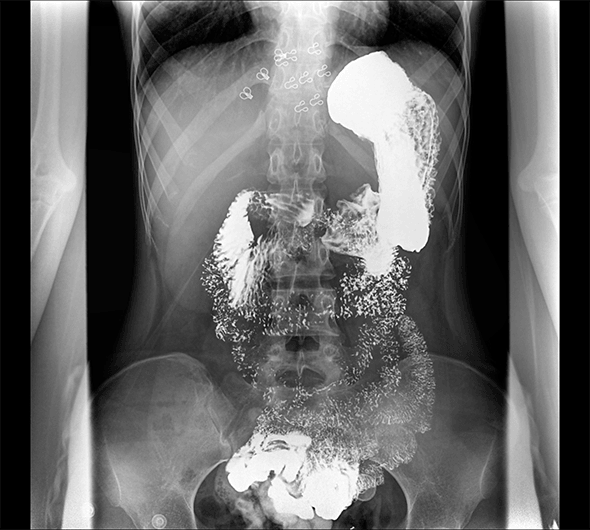

臨床圖像

創新動態斷層多功能胃腸 DR 系列